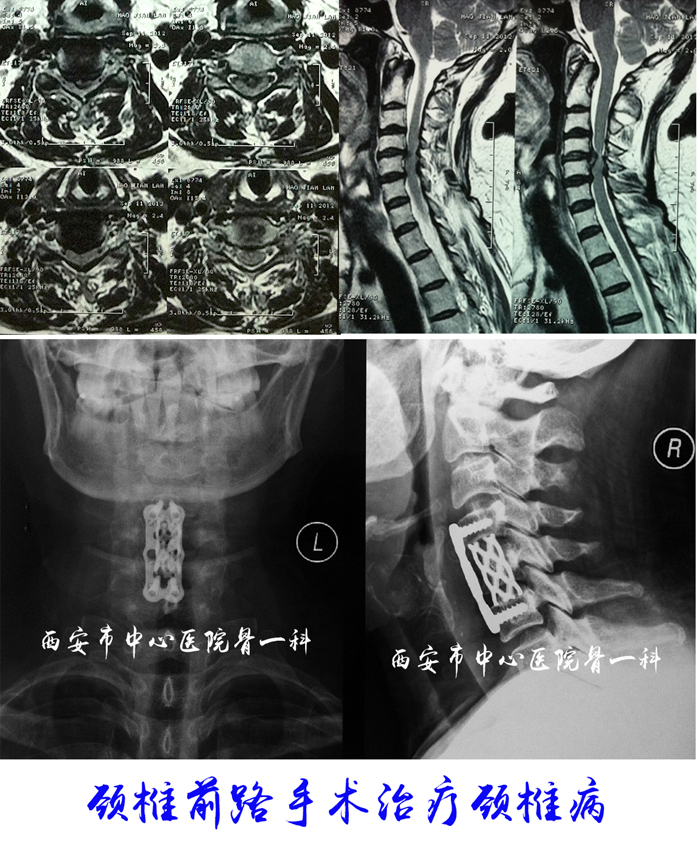

颈椎病